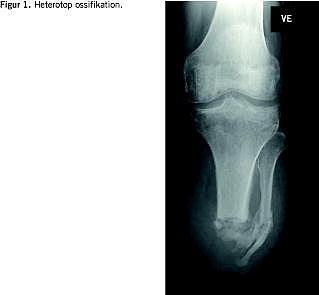

I. En 48-årig mand havde svære kroniske smerter i venstre crus som følge af posttrombotisk syndrom. Efter crusamputation blev det postoperative forløb kompliceret af infektion og gentagne reoperationer. Ved kontrol tre måneder efter udskrivelse havde patienten diskrete fantomsmerter og begyndende neurogene smerter i stumpområdet. Stumpcikatricen var reaktionsløs. Der fandtes betydelig palpationsømhed medialt fortil. En røntgenundersøgelse viste en stor, spids synostose distalt mellem fibula og tibia på samme sted som ømheden. En del af knoglenydannelsen udgik fra bløddelene (Figur 1 ). Synostosen excideredes, og man løsnede en nervegren, der var fast indlejret i knoglekonglomeratet. Knoglekonglomeratet blev fjernet, og indomethacinbehandling blev påbegyndt. Ved en opfølgning seks måneder senere var patienten smertefri. Ved en kontrolrøntgen sås der ingen tegn på heterotop ossifikation.